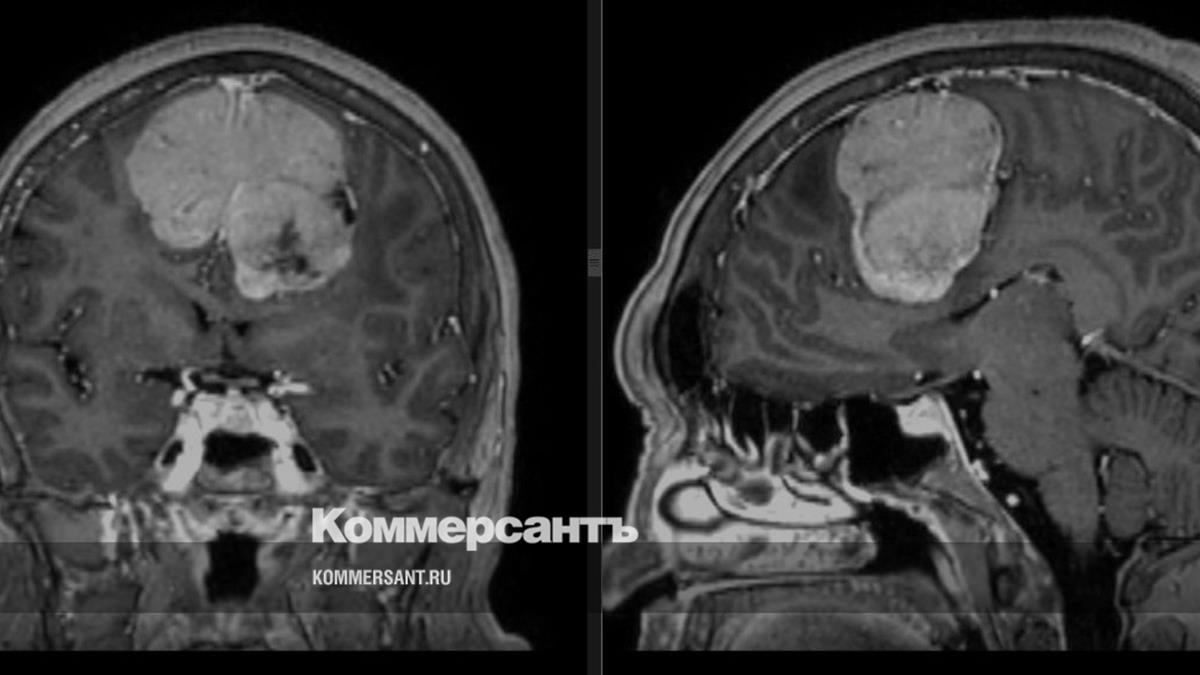

Нейрохирурги в Ижевске прооперировали пациентку с крупной опухолью мозга

Нейрохирурги ГКБ №7 в Ижевске прооперировали 60-летнюю жительницу с крупной опухолью мозга. Как сообщает пресс-служба минздрава Удмуртии, новообразование занимало почти 14% объема полости черепа — 189 куб. см.

Фото: Пресс-служба минздрава Удмуртии

Пациентка долго не обращалась к врачам, страдала от головных болей, наблюдалось ухудшение памяти, внимания. «Родственники отправили ее на обследование, где была выявлена опухоль мозга — менингиома больших размеров. Было принято решение о проведении операции, которая длилась более 5 часов»,— рассказала врач-нейрохирург Ольга Мурашова.